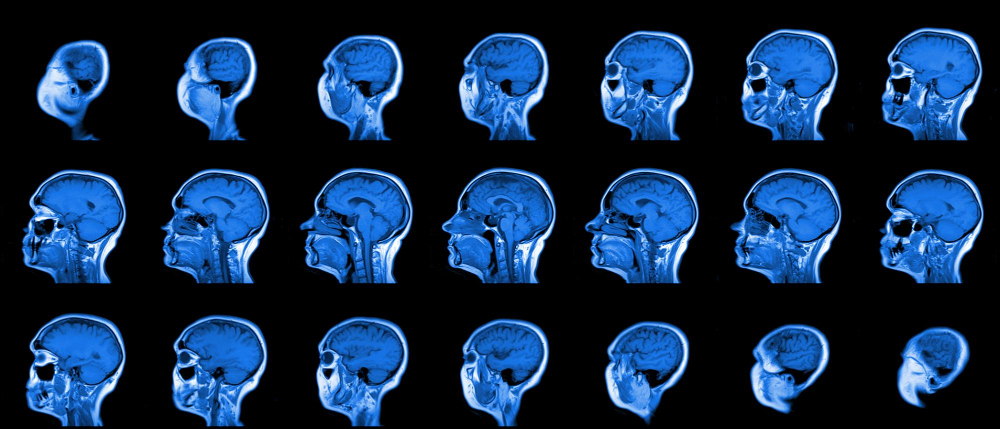

Imaging Tests

Visualizing the Brain's Condition

- CT Scans: Computed Tomography (CT) scans are pivotal in the TBI diagnostic process, providing a detailed view of the brain to identify fractures, bleeding, bruising, or blood clots. Due to their speed and availability, CT scans are typically the first imaging test performed in emergency settings.

- MRIs: Magnetic Resonance Imaging (MRI) offers more detailed images of the brain compared to CT scans and is particularly useful in assessing the extent of brain damage, including detecting subtle injuries that a CT scan might miss. MRIs are often utilized in the follow-up phase to evaluate the brain's healing progress.